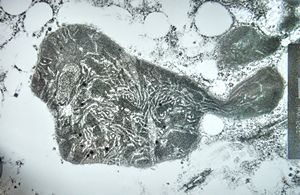

F,32y. | M. Gaucher